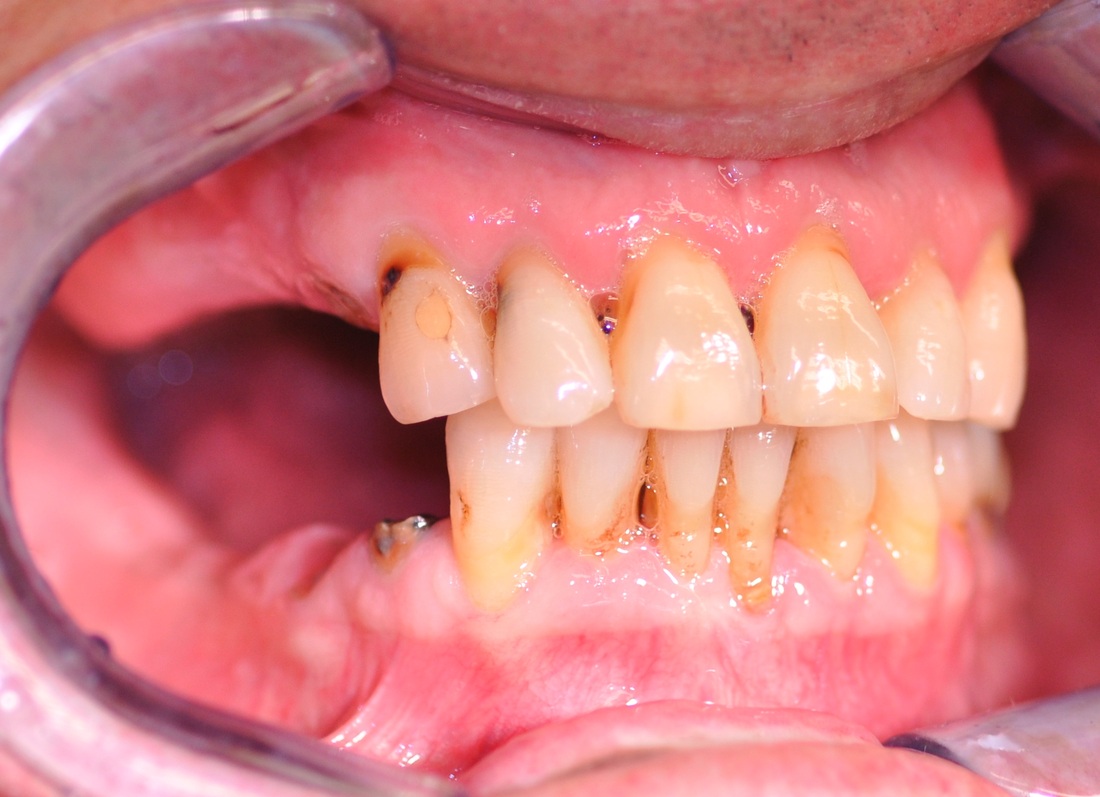

COMPREHENSIVE DENTAL REHABILITATION

A patient presented with partial teeth loss, periodontal disease, vertical bite collapse, wear on remaining teeth and smile issues.

The patient also suffered from frequent headaches, sore neck muscles, pain and clicking in both TMJs. After thorough and comprehensive evaluation- including neuromuscular diagnostic workup- a new physiological bite was established.

Missing teeth were replaced with dental implants. Teeth, damaged by bruxism (clenching and grinding), were restored with new myobite using all-ceramic veneers and crowns. During his 3-year follow-up visit the patient reported no headaches and no pain in the TMJs, improved sleep and dramatically decreased soreness of the neck muscles.